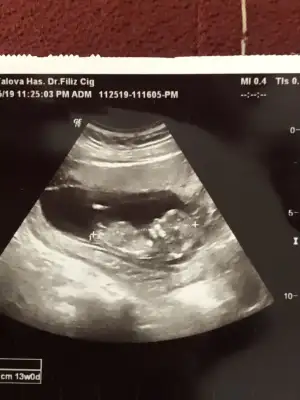

Bunlar 12 hafta usg sizce nedir cinsiyet ikra hanımmm çok heycanlıyım doktor bişey söylemedi 😌